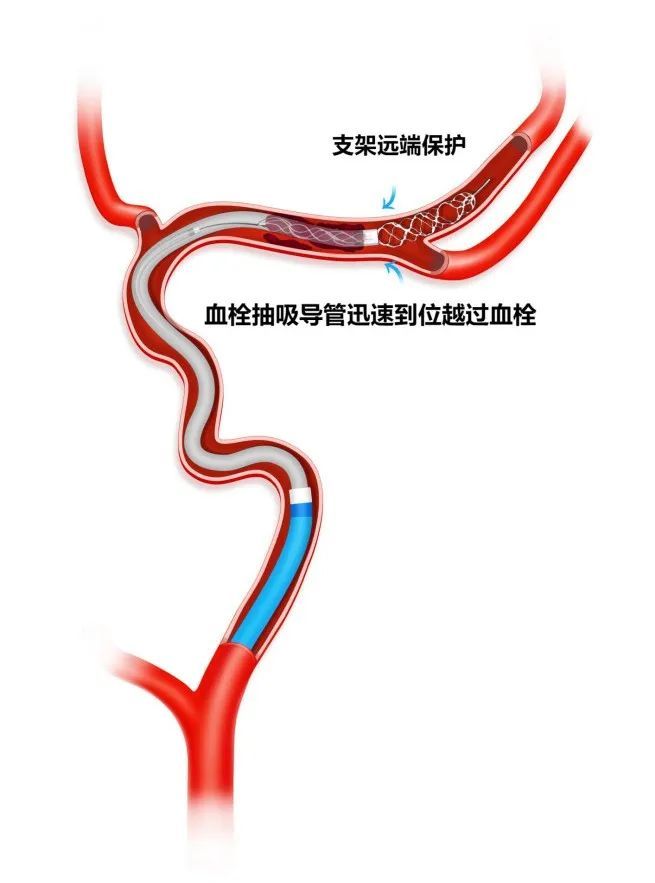

AOSIS技术(Acute large vessel OccluSion recanalization with the Intracranial protection of Stent retriever,颅内取栓支架保护下的急性大血管闭塞开通术)是基于加奇生物 Syphonet®取栓支架的独特设计特点而衍生出的针对急性大血管闭塞开通实施颅内保护的技术,在颅内动脉急性闭塞,血栓抽吸导管新手很难到位接触抽吸血栓,取栓过程容易栓子逃逸问题,利用3.0*25mm Syphonet®取栓支架作为颅内保护装置在闭塞血管远端锚定,支架远端有网篮设计,可以捕获逃逸血栓而起到保护伞的作用,近端跟进Tethys AS®血栓抽吸导管至血栓近端,关闭滴注打开血栓抽吸导管Y阀状态下越过血栓,回收支架至血栓抽吸导管内,最后将Syphonet®及Tethys AS®整体撤出。同时,Syphonet®取栓支架适配0.017、0.021inch的微导管,较小的微导管超选后,可直接将支架输送至远端释放,锚定支撑能力较强。

3.0*25mm Syphonet®取栓支架远端保护,预防抽吸术中血栓逃逸,提高手术安全性。

Syphonet®取栓支架输送导丝作为工作支撑导丝,让Tethys AS®血栓抽吸导管通过性能提高,血栓抽吸导管到位接触和越过血栓能力大大提高。目前的取栓手术中,血栓抽吸导管能不能迅速到位接触血栓和越过抽吸是血管快速再通成功的关键。

沿17或21系列微导管输送并释放3.0*25mm Syphonet®取栓支架,支架近段覆盖大脑中动脉闭塞病变部位,支架远端到达大脑中动脉M2。利用Syphonet®取栓支架的锚定作用和远端防血栓逃逸保护作用。

Syphonet®取栓支架锚定作用下跟进Tethys AS®血栓抽吸导管,靠近血管病变处开始关掉滴注,打开血栓抽吸导管Y阀后,越过大脑中动脉闭塞处到达大脑中动脉M1段末端。

负压下将Syphonet®取栓支架撤回Tethys AS®血栓抽吸导管内。

负压下将Syphonet®取栓支架和Tethys AS®血栓抽吸导管一起撤出,造影确认再通后结束手术。

右侧大脑中动脉M2段在远端3.0*25mm Syphonet®取栓支架保护下,6F Tethys®中间导引导管越过抽吸取栓。

手术示意图

本例全程在局麻下完成,术中我们采取AOSIS技术来进行本例开通血管,远端取栓支架锚定,利用Syphonet®取栓支架抓捕篮作为保护,近端Tethys AS®血栓抽吸导管关闭滴注越过血栓进行抽吸取栓,这样使血栓抽吸导管迅速到位充分接触血栓,并且远端有取栓支架保护,减少血栓逃逸的风险,极大提高血管再通效率,实现安全开通。